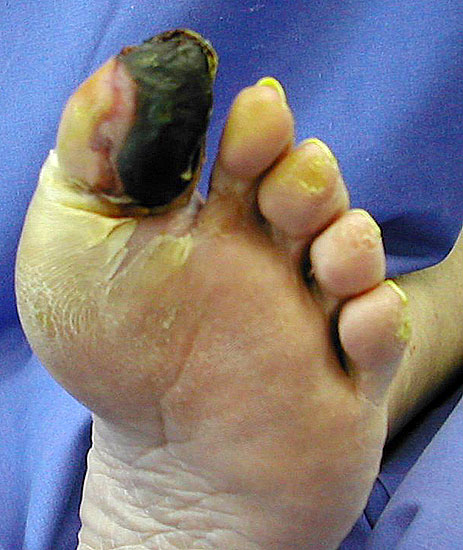

Seltene Indikationen:

• der nachvollziehbare Wunsch von multimorbiden Patienten nach einer kurzen Heilungszeit bzw. nach einer baldigen Belastbarkeit,

• wenn bei schweren Begleiterkrankungen v.a. bei höher gradiger Herz- oder Niereninsuffizienz rekonstruktive Behandlungen zu riskant oder nicht möglich sind;

• ungünstige Amputationssituationen, die keine angemessene schuh- oder orthopädietechnische Versorgung erlauben (Abb. 3).